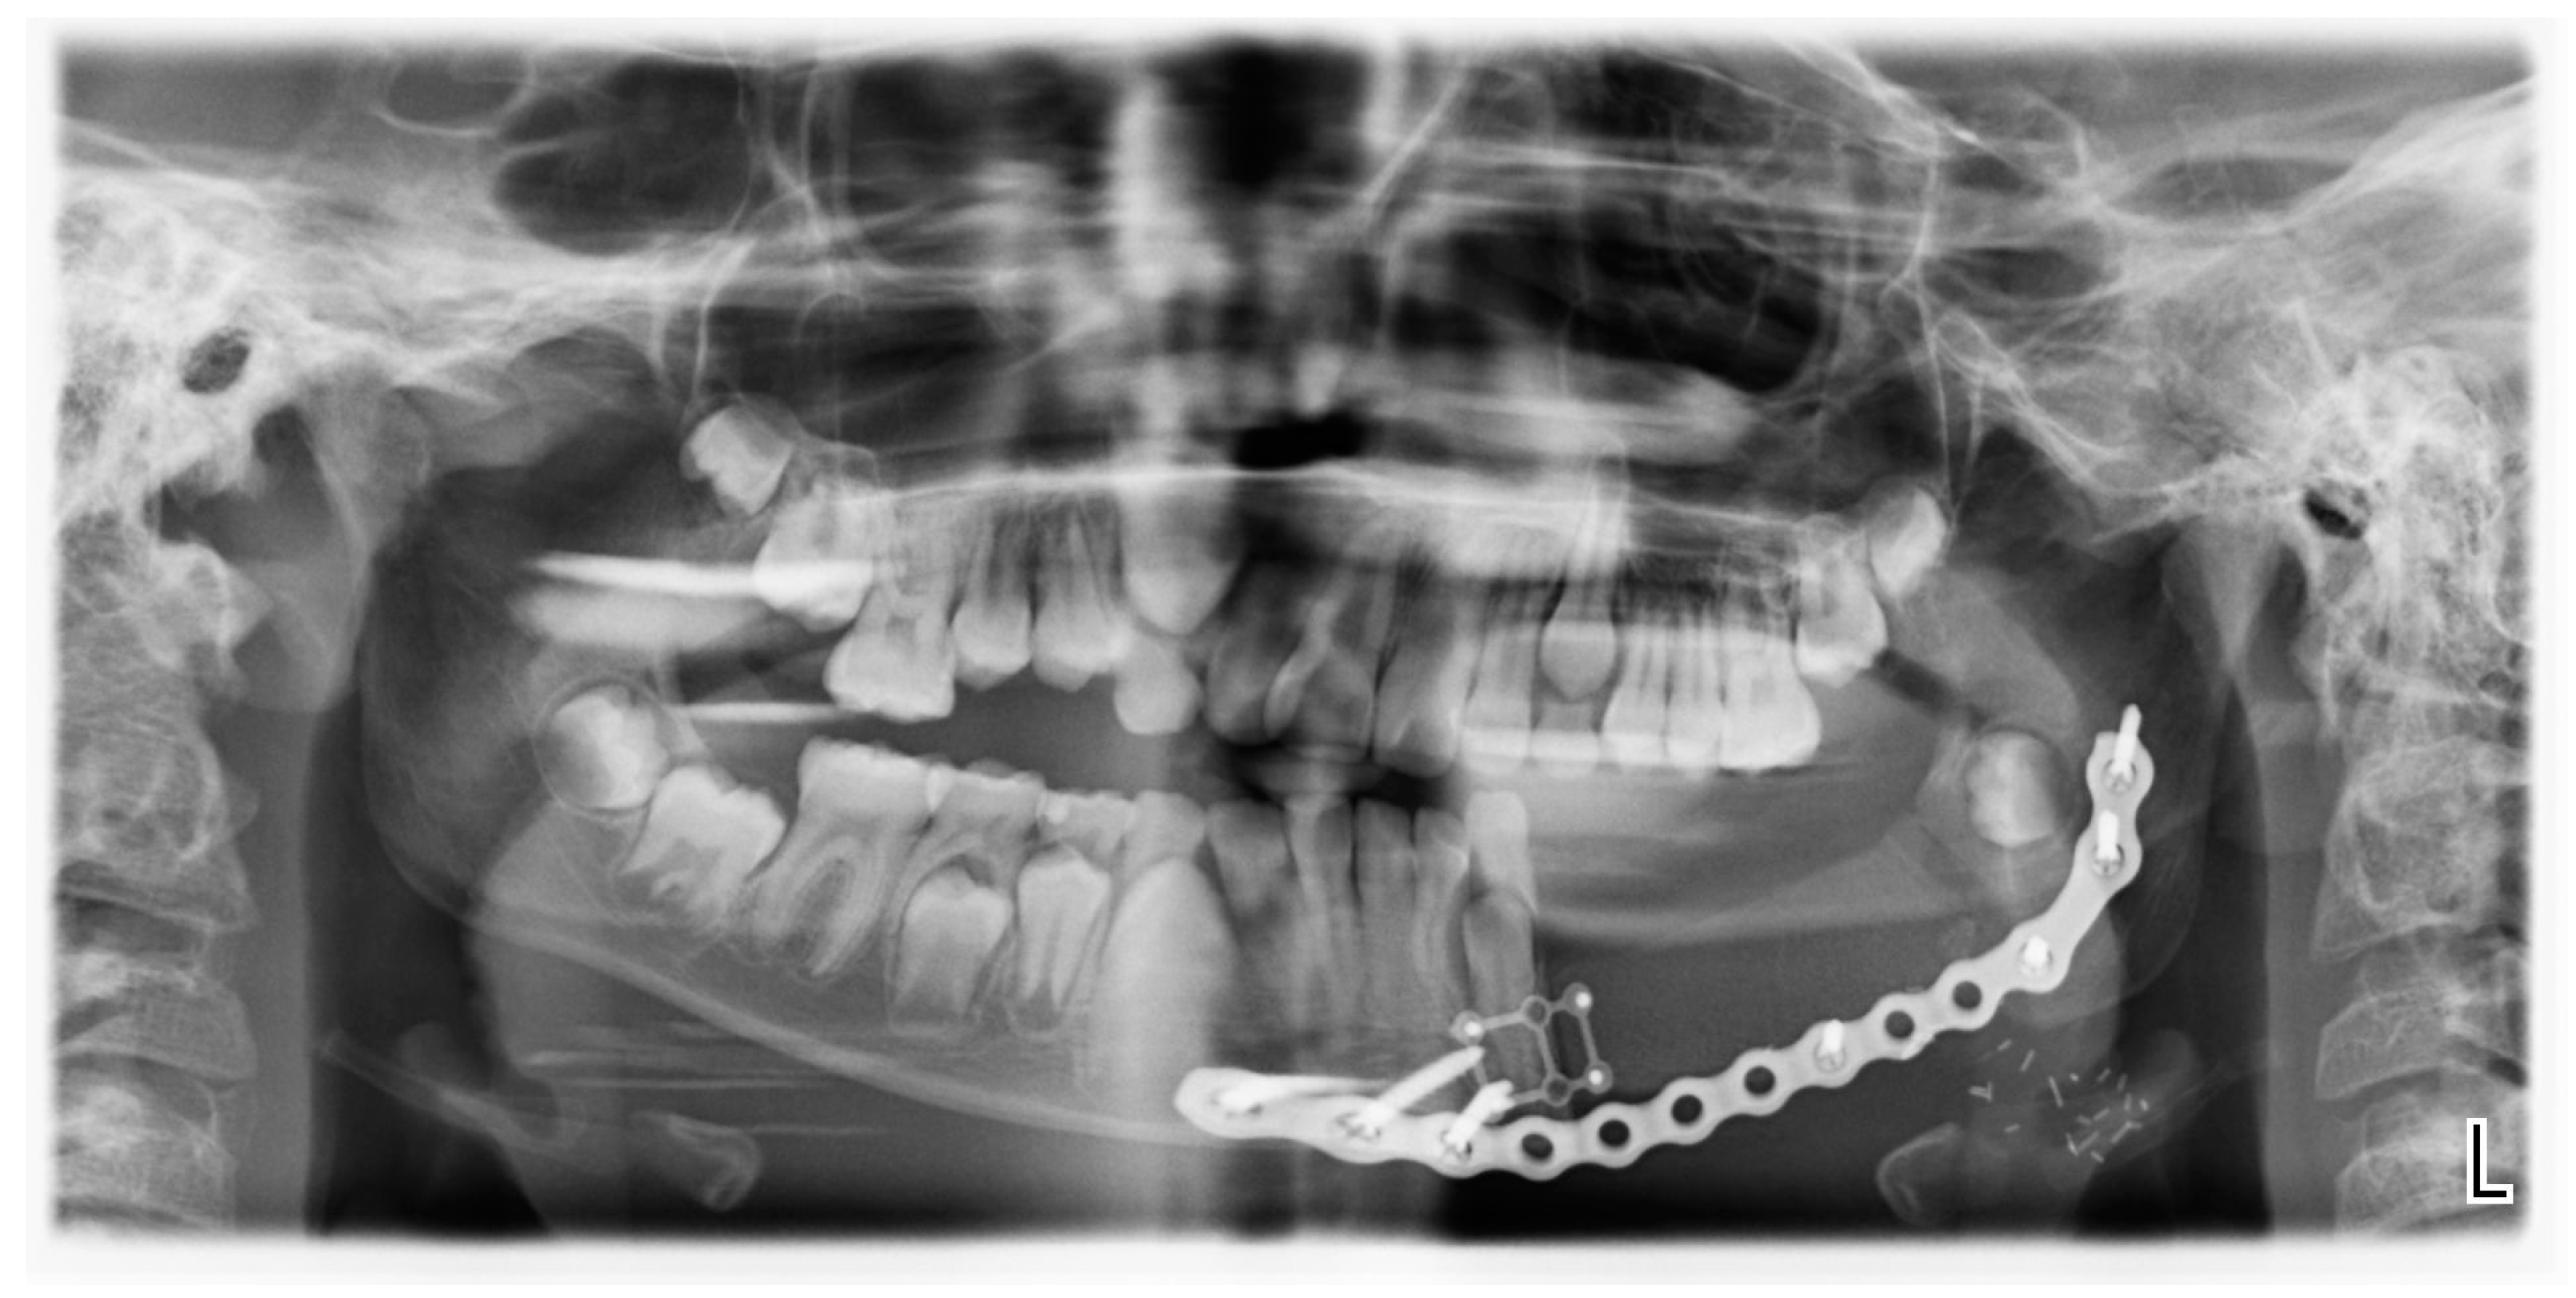

Three months after the initial diagnosis, the patient underwent segmental mandibular resection with nerve lateralization and immediate reconstruction using a deep circumflex iliac artery (DCIA) flap. An intraoral approach provided access to the affected mandible, allowing for a segmental resection with clear margins. The inferior alveolar nerve was carefully preserved and repositioned to maintain sensory function. For reconstruction, a vascularized iliac crest bone flap was harvested, contoured to match the mandibular defect, and secured with titanium plates (Figure 2 and Figure 3). Next, microvascular anastomosis was performed to the facial artery and vein using a small submandibular incision.

Despite the edentulous state of the posterior left mandible, mandibular growth progressed regularly without the development of consecutive malocclusion. However, as skeletal maturity had not yet been fully reached, the patient expressed the need for dental rehabilitation six years later. Given the absence of dentition in the transplanted DCIA free flap, the indication for wisdom tooth autotransplantation was established. The left and right impacted mandibular third molars were selected as donor teeth and transplanted into the edentulous region. They were secured using flexible dental splinting with a titanium trauma splint (TTS) (Figure 4).

Figure 2. Postoperative OPG after segmental resection and DCIA free flap reconstruction.

Figure 4. OPG after TTS removal.